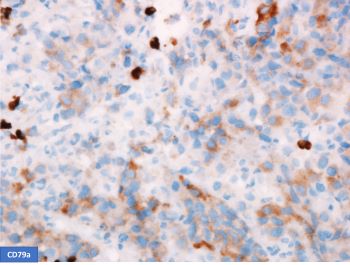

A 52-year-old man with HIV presents with weight loss and supraclavicular mass. Biopsy shows large, atypical cells with the following phenotype: CD45+, CD20-, PAX5 weak, CD3-, CD15-, CD138-, EBER-ISH+. H&E and stains for CD30 and CD79a are shown.

This is a case of EBV-positive diffuse large B-cell lymphoma associated with immune deficiency with an unusual phenotype. B-cell markers are downregulated with negative CD20 and weak expression of PAX5 and CD79a. The unusual phenotype combined with CD30 positivity raises the possibility of Classic Hodgkin lymphoma (CHL). However, the neoplastic cells are positive for CD45 and negative for CD15, making CHL unlikely. Plasmablastic lymphoma was excluded by CD138 negativity.